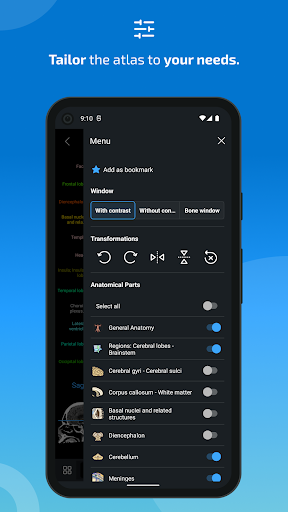

- يمكنك الآن إخفاء الهياكل واحداً تلو الآخر (زر جديد داخل نافذة الوصف المنبثقة) وعرضها مرة أخرى في القائمة الصحيحة

- يمكنك الآن استخدام قائمة الإعدادات والتمرير عبر الصور في نفس الوقت على الأجهزة اللوحية

- معلمة جديدة في قائمة المشغل لإخفاء النقاط التشريحية بدون تعليق.